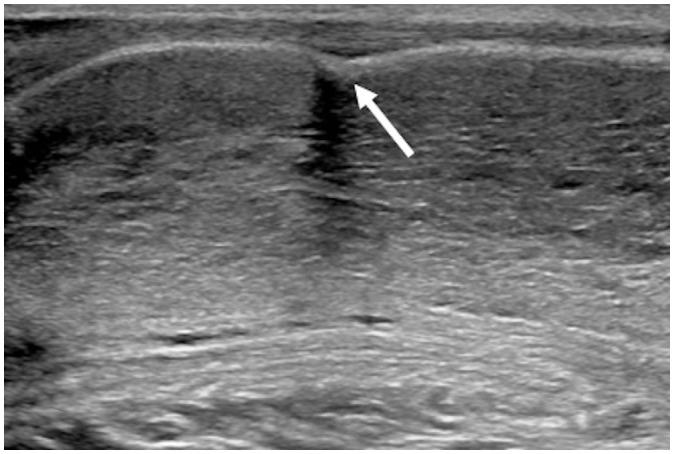

Penile emergencies are uncommon and can be categorized as having infectious, vascular, traumatic, or multifactorial etiologies. To facilitate early diagnosis and treatment during emergency, US and color Doppler imaging are imperative. US depicts hypoechoic collections regardless of the presence of air foci in infections like abscess and Fournier's gangrene. Color Doppler imaging is conducted to evaluate vascular conditions such as penile Mondor disease (PMD) and priapism. PMD is indicated by the absence of color flow and non-compressibility of dorsal penile vein. Priapism can be categorized based on cavernosal artery flow: high flow and low flow. In traumatic injuries like penile fracture, US reveals breach in tunica albuginea with hematoma. Peyronie's disease can be multifactorial in origin and the imaging is commonly visualized as thickening of the tunica albuginea and echogenic calcified plaques. Urethral injuries are urethral discontinuity with adjacent collection. Urethral calculus is visualized as echogenic focus with posterior acoustic shadowing. Therefore, effective collaboration between radiologists and urologists is required for appropriate initial diagnosis and prompt treatment.

阴茎急症并不常见,可分为感染性、血管性、创伤性或多因素病因。为便于在急诊时进行早期诊断和治疗,超声(US)和彩色多普勒成像必不可少。在诸如脓肿和福尼尔坏疽等感染中,无论是否存在气灶,超声均能显示低回声液性聚集。进行彩色多普勒成像以评估血管状况,如阴茎蒙多氏病(PMD)和阴茎异常勃起。阴茎蒙多氏病表现为阴茎背静脉无血流信号且不可压缩。阴茎异常勃起可根据海绵体动脉血流分为:高流量型和低流量型。在阴茎骨折等创伤性损伤中,超声显示白膜破裂并伴有血肿。佩罗尼氏病的病因可能是多因素的,影像学表现通常为白膜增厚和回声增强的钙化斑块。尿道损伤表现为尿道连续性中断并伴有相邻液性聚集。尿道结石表现为伴有后方声影的回声增强灶。因此,放射科医生和泌尿外科医生之间需要有效协作,以进行恰当的初步诊断和及时治疗。